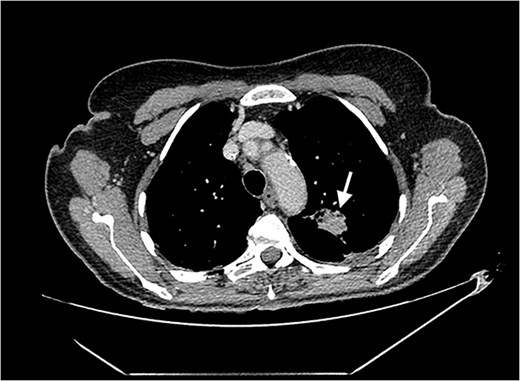

Echocardiography revealed a 1.2 cm pedunculated mass attached to the anterior mitral valve leaflet (AMVL) with severe mitral regurgitation (Fig. 1). Computed tomography imaging revealed multiple hepatic lesions (suspected septic emboli, Fig. 2), and a cavitating mass in the posterior aspect of the left upper lobe of the lung (Figs 3 and 4). Magnetic resonance imaging showed multiple cerebral lesions (Fig. 5), also thought to be septic emboli. Her presentation was suspected to be due to infective endocarditis rather than ischaemic, as troponin was negative, and coronary angiography was unremarkable. She was therefore treated promptly with intravenous vancomycin and gentamicin as per local antimicrobial guidelines. However, she failed to recover, and her case was reviewed in the regional in-house urgent cardiac surgical multidisciplinary team meeting. Considering her persistent fever, as well as the recurrent emboli, the decision was made to transfer her to our centre for emergency surgery.

Axial CT image of the lungs, showing a cavitating mass in the posterior aspect of the left upper lobe, suggestive of an abscess secondary to infective endocarditis.